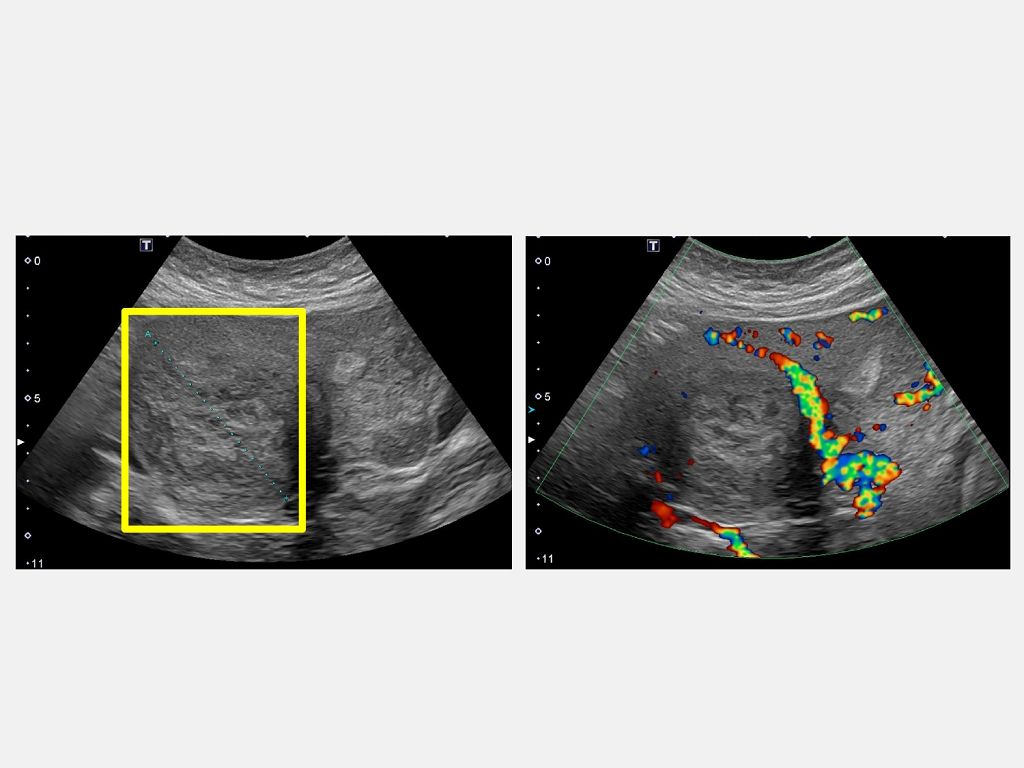

45歲的魏女士因為近半年來出現下腹部悶痛,所以到仁愛長庚合作聯盟醫院(大里仁愛醫院)婦產科林玉珊醫師門診求診,檢查後發現有下腹部悶痛合併壓迫症狀,竟然有7公分的肌瘤。經採用達文西機械手臂系統結合經陰道自然孔手術,於術後一週後即返家休養。由於手術並未在腹部留下傷口,讓魏女士感到非常驚訝,林玉珊醫師表示,傷口只是藏在看不到的地方,這不只是手術傷口變小,更代表病人能更快回到自己的生活與角色中。

林玉珊醫師指出,傳統腹腔鏡手術雖屬微創方式,但仍需在腹部開設多個小切口。經陰道自然孔手術是利用陰道作為自然通道進入骨盆腔,完全免除腹部傷口。第四代達文西機械手臂系統的高解析3D影像讓骨盆腔結構更清楚,機械手臂能在極狹小的空間中完成精細的分離與縫合。病人出血量少、疼痛感輕微,大多數人隔天即可下床,恢復速度比傳統手術明顯更快。

林玉珊醫師說,經陰道自然孔手術雖創傷小,但傳統操作對醫師姿勢與體力要求高。第四代達文西機械手臂系統讓醫師能以坐姿操作控制台,透過細微手指動作即可精準帶動機械手臂。在手術過程中鏡頭穩定、視野清晰,醫師不再需要長時間維持高強度姿勢,能把專注力放在每個細節上,這讓手術更安全,也更優雅。

林玉珊醫師表示,她與院內婦癌及婦女泌尿科醫師密切合作,依據不同病症選擇最適合的手術方式。第四代達文西機械手臂系統讓醫師能在同一系統下執行多種婦科手術,從良性腫瘤切除到婦癌手術、婦女泌尿手術,都能更精確、出血更少,這對病人與醫師都是雙贏。而經陰道自然孔手術主要適用於子宮全切除、特定位置的激流切除及卵巢相關手術,可在沒有腹部傷口的情況下完成治療。